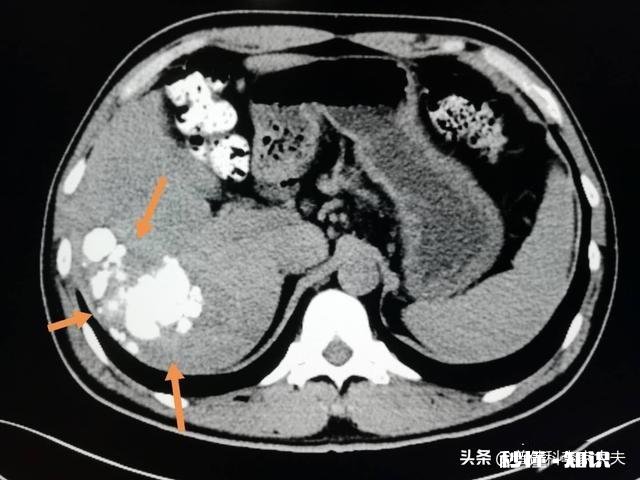

首先他的肝癌确诊是体检发现,右肝s5区发现1.5×1.9小肝癌 , 没有任何症状,但是他有小三阳,他是一直也没有太注意,因为在生意场上难免要应酬 , 喝酒是经常的,2013年3月体检发现,因为是小肝癌,有手术切除的指征,肝s5区肿瘤切除 。但是,10月份复发了 。

文章插图

后来思考复发的原因,做完手术以后情况都非常好,感觉跟正常人一样,但是他没有太注意术后用力的情况,经常负重背东西 。最后检查复发肝脏情况 , 多个小结节转化成小肝癌 。